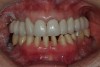

Figure 30  Final restorations.

Figure 30

Figure 31  Technical precision and artistic skill blend into pleasing smile and happy patient.

Figure 31